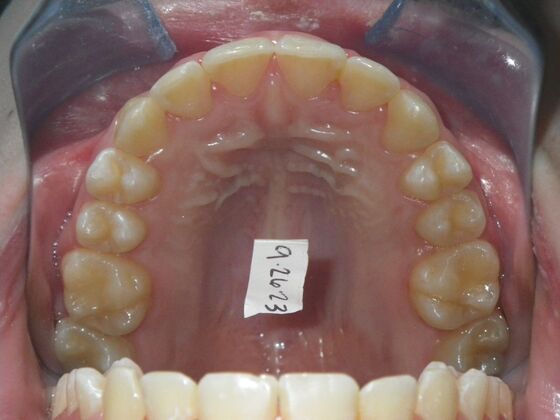

Patient presented with mixed dentition and mild deep overbite, excessive overjet,and rotated lower incisors. She also had a lower bilateral lingual retainer, preventing lower molars from coming forward. She was treated with utility archwires initially, waiting for eruption of cuspids and bicuspids. This was followed by conventional straight wire appliances and upper and lower standard hawley retainers.